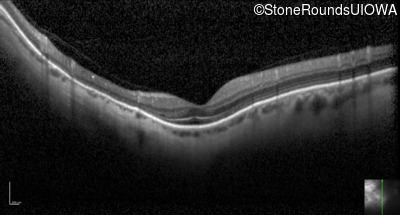

Optical Coherence Tomography - Left - 20/25 +2

Exemplar / OCT Stack

OCT Stack